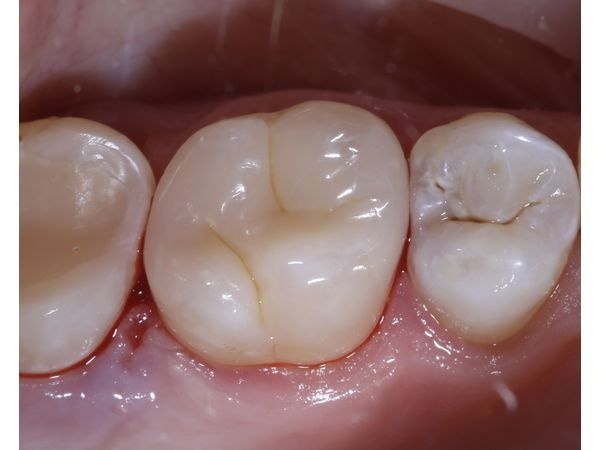

- восстановили анатомически правильную форму зуба с помощью японского пломбировочного материала, т. е. установили пломбу;

- отполировали зуб до зеркального блеска.

Через 2 недели после лечения все жалобы прошли. Кровоточивость и болезненность десны больше не беспокоили пациента.

На контрольном осмотре через полгода наблюдалась положительная динамика: все зубы были здоровы, симптомы не возвращались.